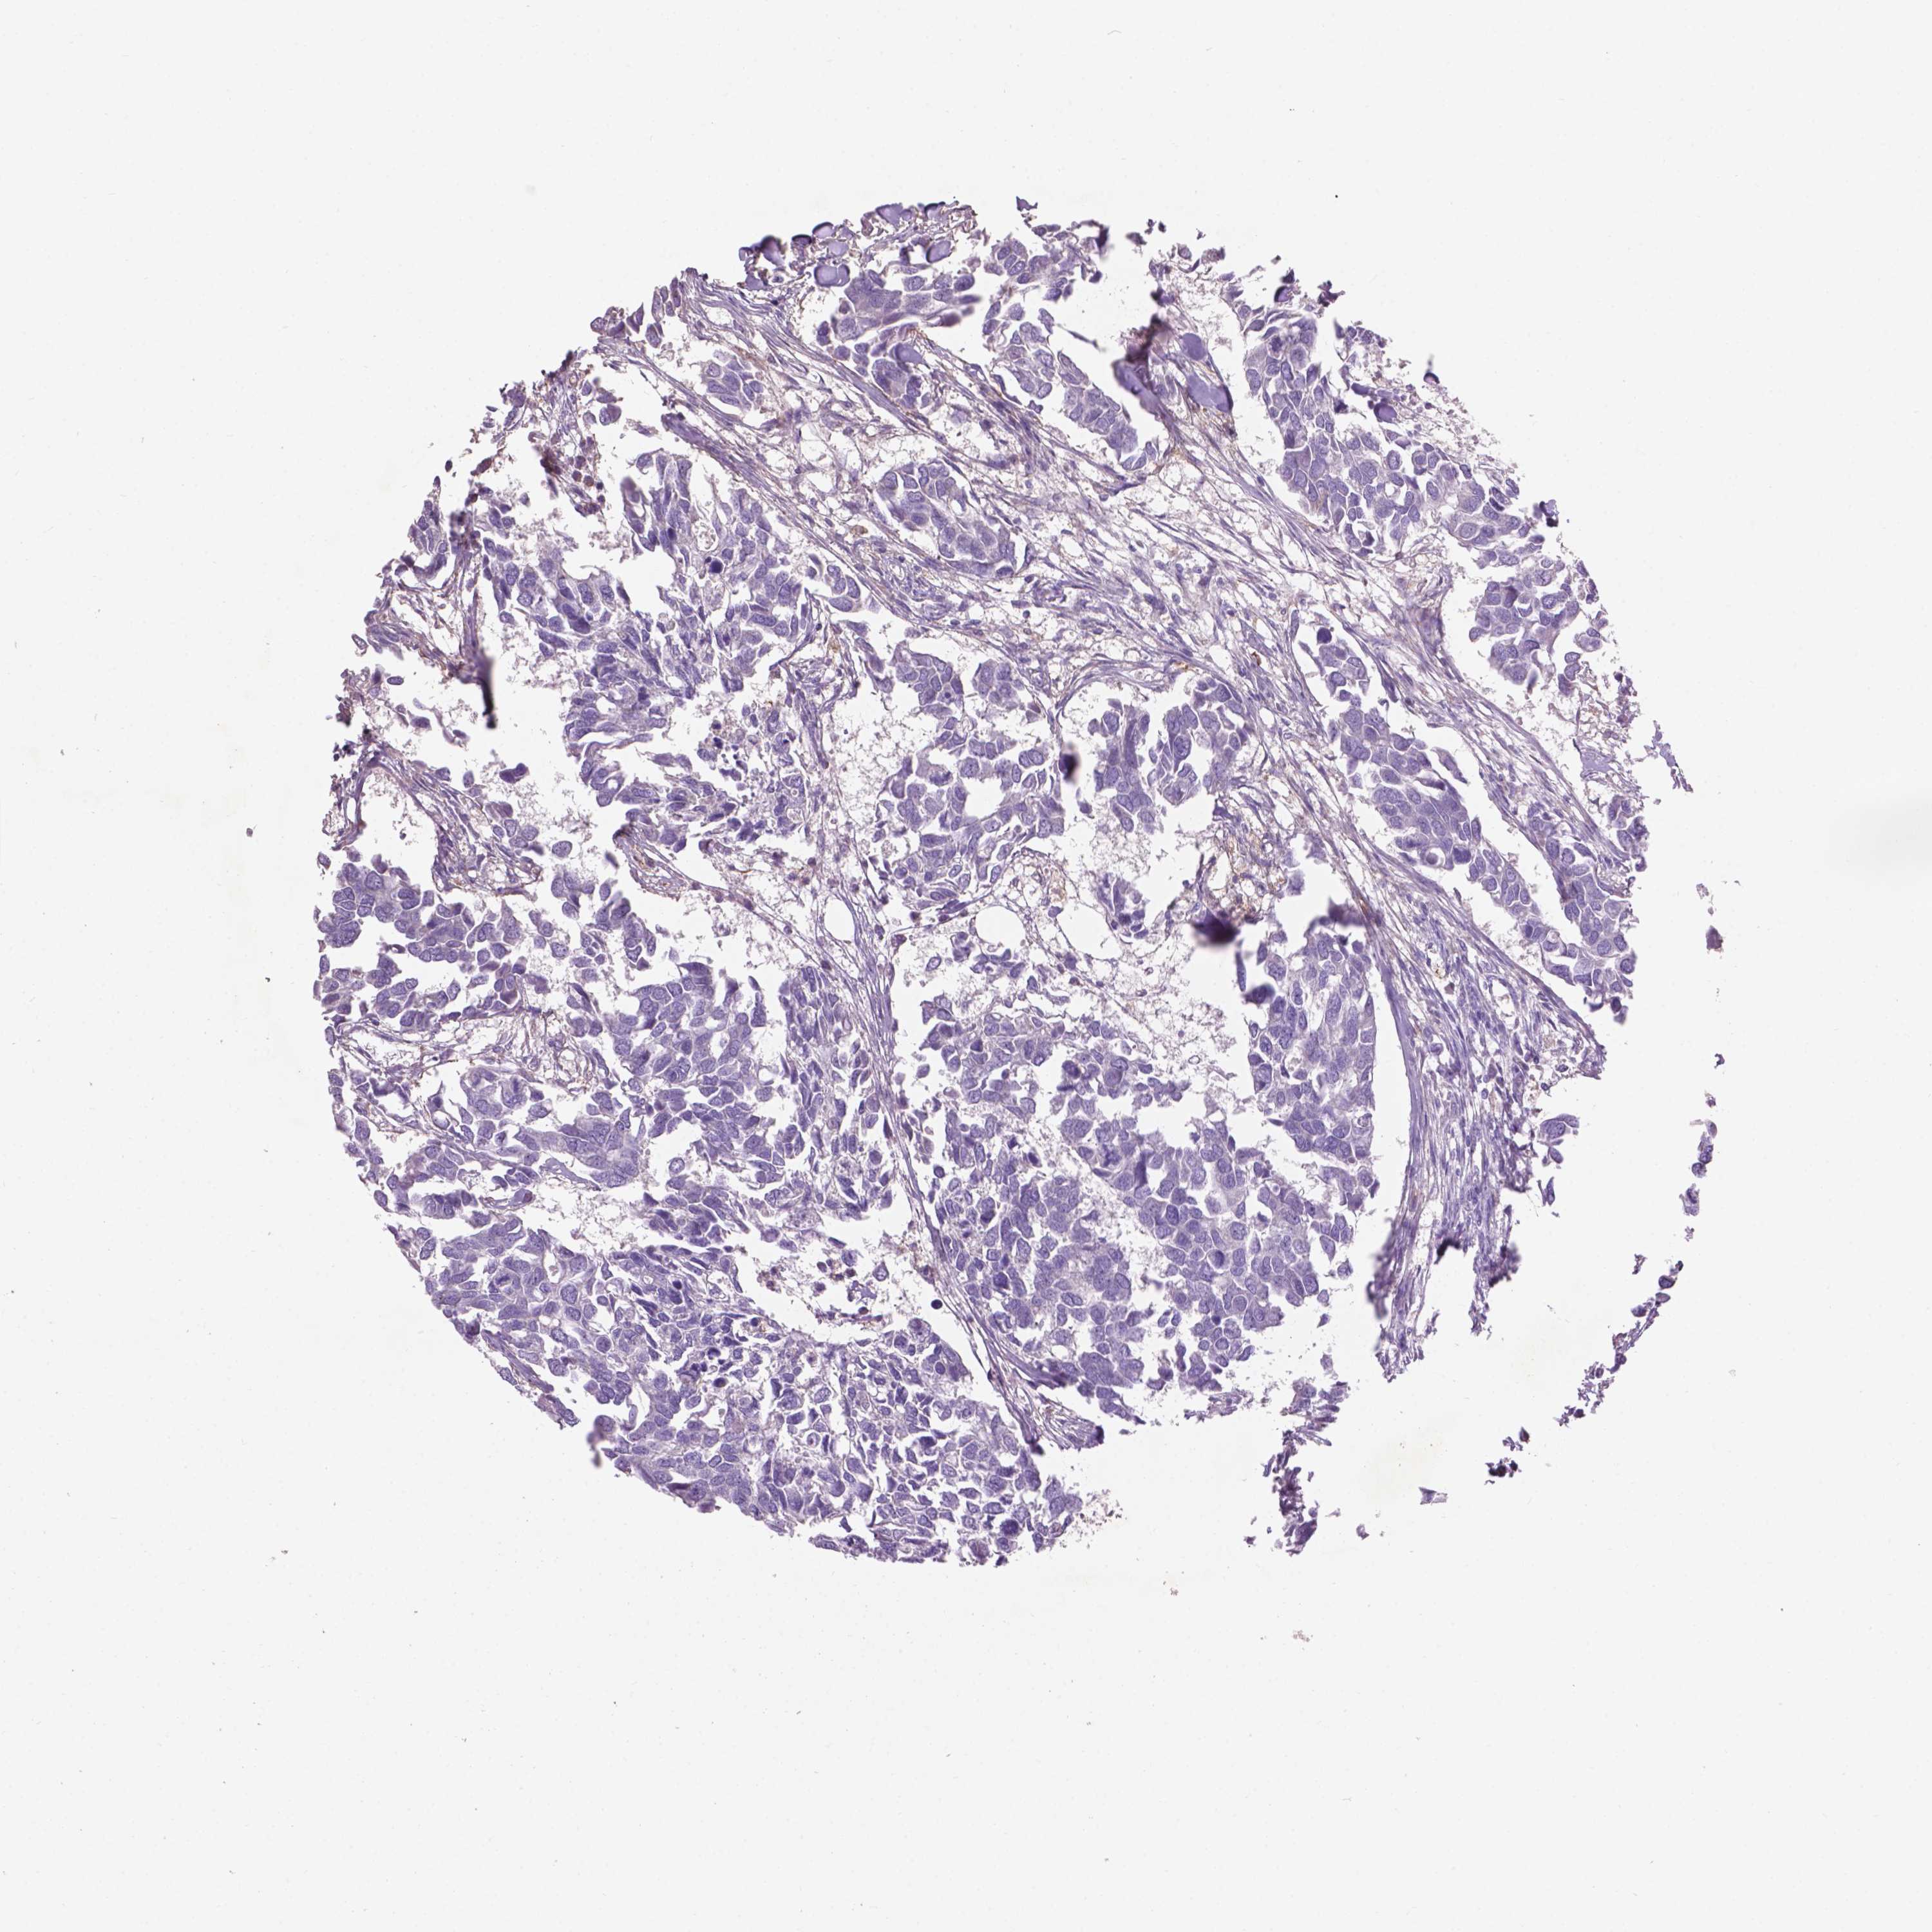

BRCA TCGA BRCA VALIDATION PROTEIN EXPRESSION

ANTIBODIES

AND

VALIDATION